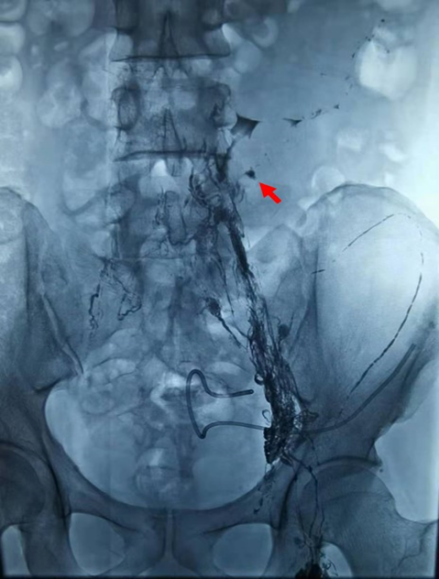

腹腔淋巴漏是由于疾病侵袭或者医源性损伤导致的腹腔淋巴管破裂,淋巴液外溢导致的疾病。淋巴漏的出现,可导致患者电解质紊乱、低蛋白血症、免疫功能下降等,甚至危及其生命。 患者术后产生少见并发症-淋巴漏 5个月前,深圳的刘先生检查出腹部恶性肿瘤,经过3周期新辅助化疗后,于今年3月接受了外科手术,但手术后却出现了一种少见的并发症——淋巴漏,术后的第6天,他的腹腔引流管中就流出了680ml乳白色的液体。经过两个月的保守治疗后收效仍不佳,每天引流管中还会流出500-1000ml不等的乳白色液体。 下腹部的坠胀、偶尔伴有疼痛,期间还因引流管堵塞、脱落反复穿刺腹腔引流……这些症状都严重影响了顽固性淋巴漏患者刘先生的生活质量。 介入治疗前引流液颜色为乳糜样液体 介入微创治疗顽固性淋巴漏 据主管医生介绍,约70%~80%的淋巴漏患者经禁食等保守治疗后可自愈。对于保守治疗效果不佳的难治性患者,传统的治疗方法是再次手术,但手术存在着一定难度与风险,甚至可能会失败。 面对这样的情况,777全讯白菜网立即组织开展多学科讨论,决定通过介入微创的方法来治疗顽固性淋巴漏。经过多学科充分的讨论与严谨的评估,介入治疗科副主任宋鹏为刘先生制定了严密的手术计划和诊疗方案——超声引导下穿刺腹股沟淋巴结,然后进行淋巴造影,造影确定漏口后进行淋巴漏的栓塞。 2021年6月9日,在介入治疗科副主任宋鹏和超声科医生的密切配合下,刘先生的左侧腹股沟淋巴结被成功穿刺,连接注射器缓慢注射造影剂,通过每间隔3-5 分钟摄影,大约1小时左右淋巴管破口也被顺利地找到。在宋鹏主任的精细操作下,一根纤纤细针穿过刘先生的腹腔,精准穿刺到漏口部位,随着微导管对缺口位置再次确认及生物胶的缓缓注入,淋巴管的破口被成功封堵,手术取得了圆满成功。 淋巴结造影找到破裂口 (红色箭头 ) 栓塞之后破口完全封堵 治疗效果立竿见影,患者恢复正常生活 令刘先生惊喜的是,手术全程非但没有特别的疼痛与不舒服,治疗效果还立竿见影。第二天,引流液明显减少,颜色由原来的乳白色变为淡黄色;第三天,复查CT结果显示,腹盆腔积液完全消失;术后1周,伴随刘先生两个多月的引流管被拔掉,患者恢复了正常生活。 介入治疗后引流液颜色为清亮液体 科普小课堂 淋巴漏介入治疗是近几年国际上新发展的一项技术,通过淋巴管造影和辅助栓塞技术对漏口进行栓塞,创伤小,疗效确切。777全讯白菜网通过该技术,成功治疗了顽固性淋巴漏患者,属深圳市首例。 这项手术的开展,既填补了目前深圳地区利用介入方法来治疗顽固性淋巴漏的空白,同时也标志着777全讯白菜网介入治疗科在该领域达到国际同步及国内领先水平,为患者带来了福音。 医疗新动态,持续关注不掉队!